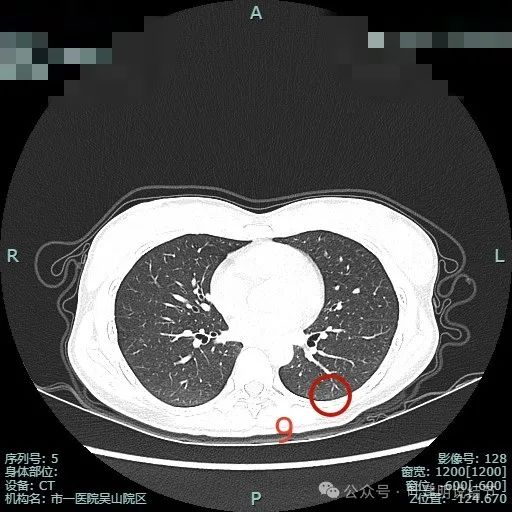

病灶9:左下叶微小淡磨玻璃结节,整体轮廓较清,考虑肺泡上皮增生或少许纤维增生可能。